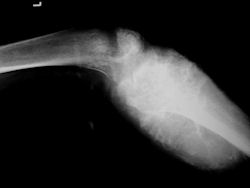

Radiographic imaging is used to help form a diagnosis of CCs. These include X-Ray, MRI, CT and Bone Scans

An example of an CC MRI is shown.